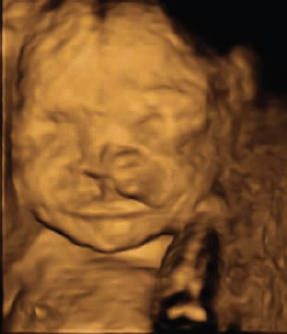

Today in the 21st century, prenatal ultrasound screening has become widely accepted for the diagnosis and documentation of the health of both mother and fetus. This has extended into developing countries. Routine two-dimensional (2D) ultrasounds are typically obtained during the first trimester to document viability. A second trimester ultrasound is performed with more emphasis on the development of the fetus ( Figs. 1.4 and 1.5 ).

Since the 1970s there has been an increasing interest in improving the images of the fetal face using ultra-sound. The fetal face is frequently not imaged adequately in the first trimester screening ultrasounds because of fetal movement or obstruction of the view by the arms and hands. Three-dimensional (3D) ultrasound images of the face were first obtained in 1986. However, 3D ultrasound did not become widely used until the mid-1990s. By 2000, multiplanar volume rendering with 3D ultrasound became possible.6 The 2007 American Institute of Ultrasound in Medicine guidelines for prenatal ultrasound screening do not require visualization of the fetal face in the first trimester ultrasound; however, the fetal face must be imaged as a minimum requirement for the second trimester screening. The use of transvaginal ultrasound screening has improved the diagnostic accuracy, but it is still far from perfect.

Technological improvements, namely 3D and four-dimensional (4D) ultrasound, have improved accuracy, and the resulting image capture photograph is more recognizable to parents; however, diagnosing the isolated CP remains problematic.19 The ultrasound literature abounds with descriptions of different techniques for the 3D/4D imaging, which have infrequently successfully detected the isolated CP.20 In addition, with volume averaging, false-positives (a cleft is detected when not present) can appear due to shadowing.10